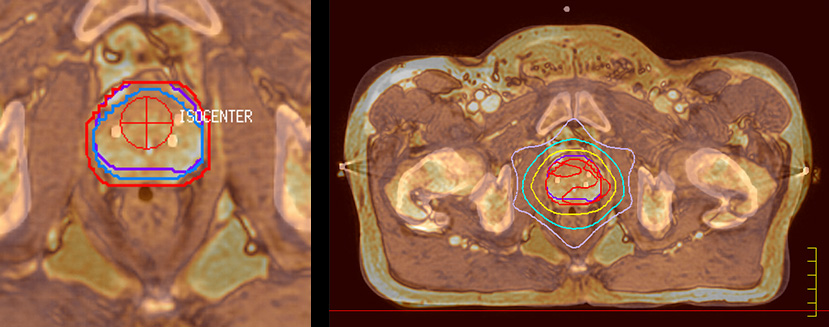

Special requirements for MRI in RT planning

“There are some general challenges in RT imaging – even with CT – such as imaging geometry and positioning accuracy. Positioning is extremely important in RT, because we need reproducibility between imaging and treatment position. We also need accurate geometry so we can be sure our treatment plan is properly delivered during the treatment,” says Dr Yan.

“The Ingenia MR-RT configuration includes an external laser positioning system for patient alignment and a flat tabletop for imaging the patient in treatment position. Ingenia MR-RT also came with a special QA package for regular monitoring of precision. Our Ingenia 3.0T scanner achieves good geometric accuracy – within a millimeter for most patients – and the phantom measurement is even better,” he adds.

“When a patient registers, first CT simulation and MR simulation are done, followed by CT-MR registration on Pinnacle3. Then the target and normal organ delineation is performed on MR images. Meanwhile we create a reference CT image for online treatment and localization correction. During the treatment phase we can perform additional MRI scans to visualize the anatomy changes and create an adaptive plan. This plan basically adapts the treatment plan to the changes.”